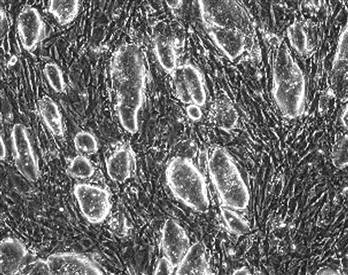

自然生長(zhǎng)的老鼠胚胎干細(xì)胞。

經(jīng)過科學(xué)家的改造,老鼠的纖維原細(xì)胞具有了胚胎干細(xì)胞的相同特征和功能。